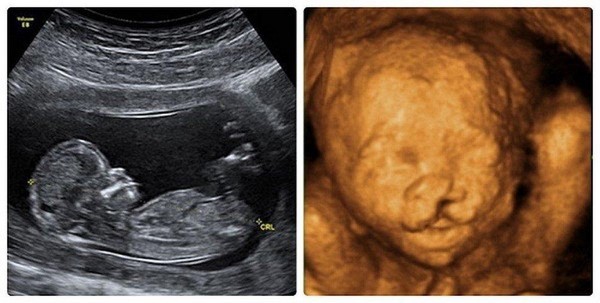

+ Siêu âm thai: Thai 27 tuần, giãn não thất, dịch màng phổi 2 bên, nghi ngờ bất thường tim, thiểu ối.

- Đối với thai nhi và trẻ sơ sinh: đái tháo đường thai kỳ ảnh hưởng lên sự phát triển của thai nhi chủ yếu vào giai đoạn ba tháng đầu và ba tháng cuối thai kỳ. Giai đoạn 3 tháng đầu, thai có thể không phát triển, sảy thai tự nhiên, dị tật bẩm sinh, những thay đổi này thường xảy ra vào tuần thứ 6, thứ 7 của thai kỳ. Giai đoạn 3 tháng giữa, đặc biệt 3 tháng cuối thai kỳ có hiện tượng tăng tiết insulin của thai nhi, làm thai nhi tăng trưởng quá mức, vàng da sơ sinh, tăng hồng cầu, béo phì và đái tháo đường trẻ em. Đối chiếu thai phụ này có 1 lần sẩy thai có thể là hậu quả của dái tháo đường thai kỳ không được phát hiện và lần mang thai này đã nghi ngờ có dị tật thai.